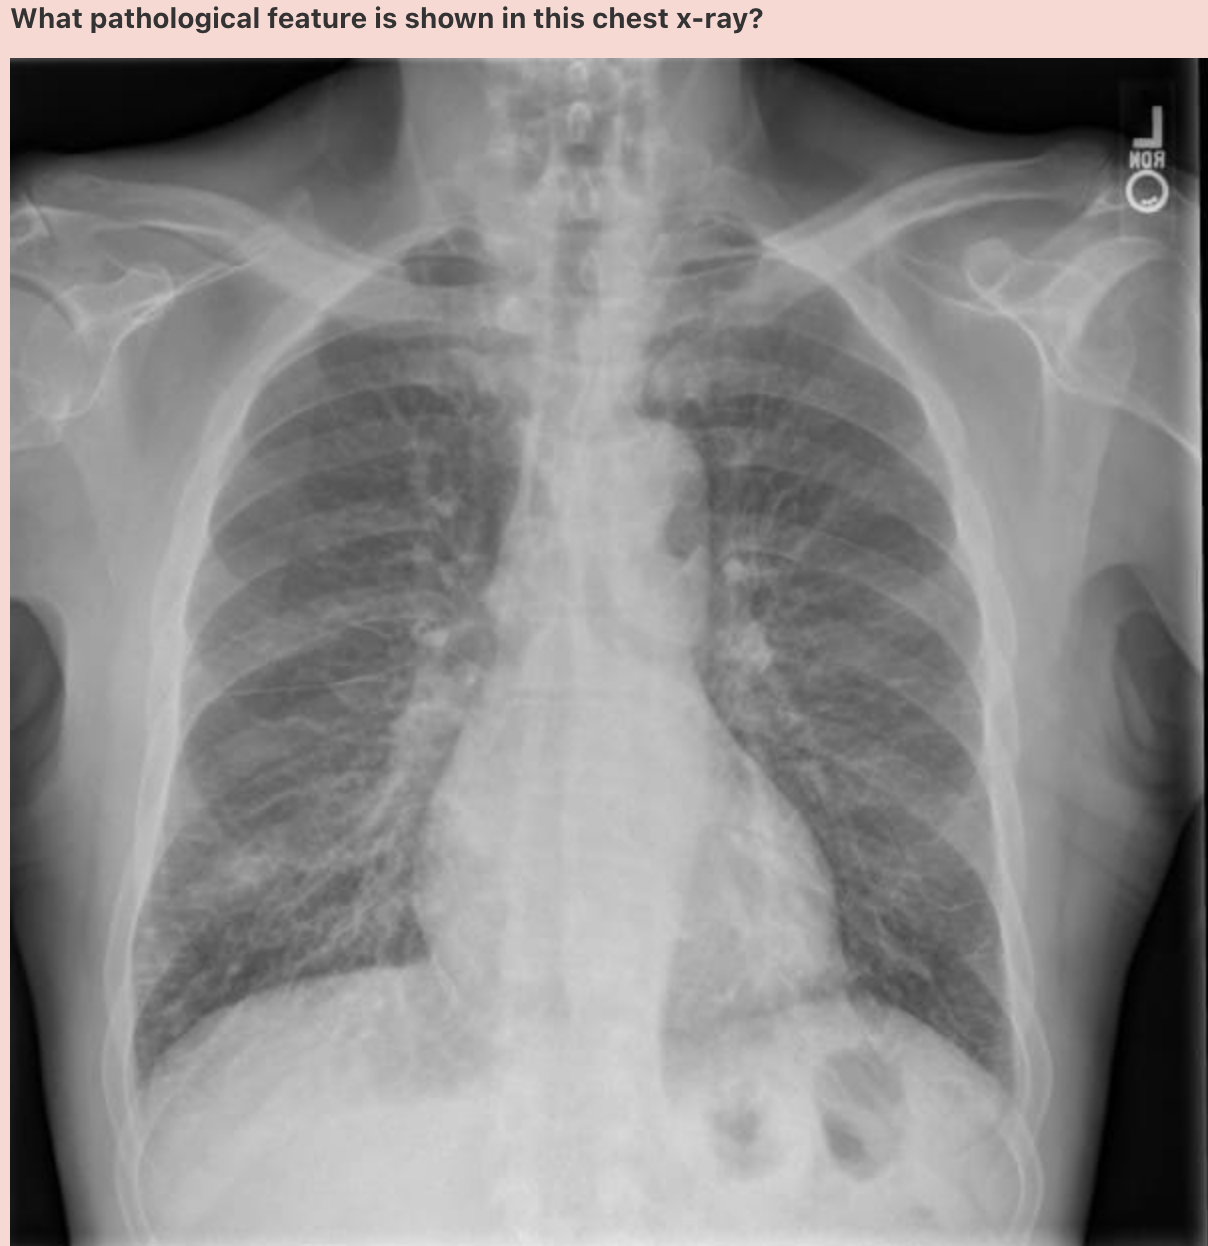

What pathology is shown in this chest x-ray?

Answer: Pulmonary oedema